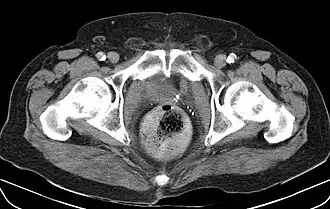

![]() Fecaloma rectal en un paciente hospitalizado. Presenta, además, una neovejiga y aterosclerosis. TC abdominal. | ||